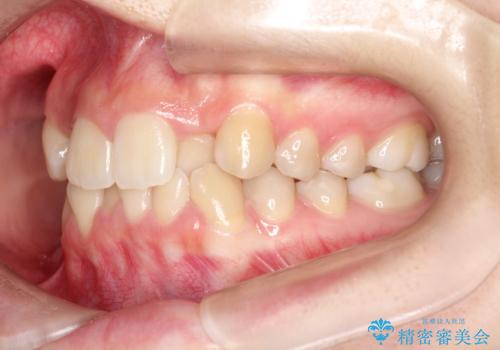

目立たない矯正で歯のデコボコと反対咬合を改善

- 前歯のデコボコ(叢生)と、前歯が上下逆の咬み合わせ(反対咬合)を主訴にご来院されました。精密検査の結果、歯列全体のスペースが不足していることが判明。患者様のご希望に合わせ、透明で目立ちにくい**インビザライン(マウスピース矯正)**による治療計画を立案しました。歯を抜かずに、歯列全体を奥(遠心)へ移動させることで、歯が並ぶスペースを確保し、叢生と反対咬合を同時に改善することを目指します。

今回の矯正治療では、透明なマウスピース型の装置インビザラインを使用しました。この装置は目立たず、取り外しが可能なため、食事や歯磨きも普段通り行えます。治療は、緻密な治療計画に基づき、段階的に作製されたマウスピースを交換していくことで、遠心移動という方法で奥歯から徐々に歯列全体を後方へ動かしました。これにより、不足していたスペースを確保し、前歯のデコボコを解消。同時に、上下の歯の前後的な関係を改善することで、反対咬合も正常な咬み合わせへと導きました。見た目も機能も改善し、自然で美しい笑顔を獲得していただけました。